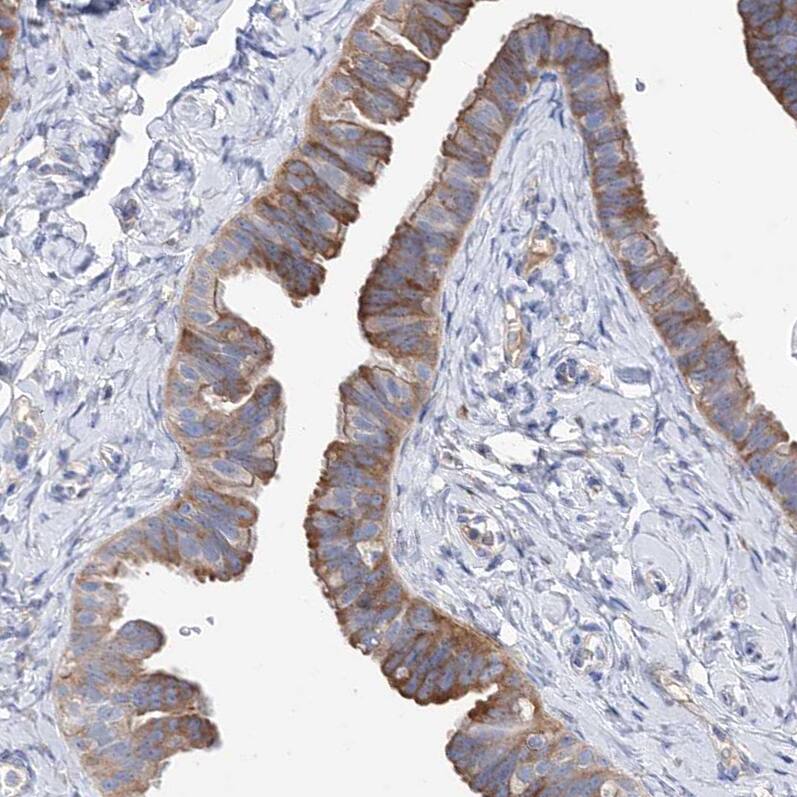

BBS4 Antibody - BSA Free Immunohistochemistry-Paraffin: BBS4 Antibody - BSA Free [NBP1-86248]

Immunohistochemistry-Paraffin: BBS4 Antibody - BSA Free [NBP1-86248]

Staining of human prostate shows strong cytoplasmic and membranous positivity in glandular cells.